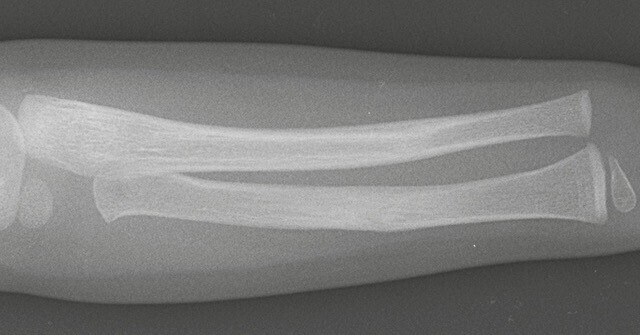

• fracture en bois vert : une corticale est pliée mais continue alors que l’autre est rompue (fig. 4) ;

• fracture « plastique » ou « arcuature » : il n’y a pas de fracture mais une courbure plastique s’étendant sur toute la longueur de l’os (fig. 5) ;

Leur diagnostic est aisé, habituellement par la réalisation de radiographies simples. Certaines fractures ont des spécificités pédiatriques liées à la moindre résistance osseuse (fracture en bois vert, fractures en motte de beurre ou fractures plastiques) ou à la présence de cartilages de croissance (fractures-décollements épiphysaires).

Il existe des fractures propres à l’enfant : fracture en motte de beurre, fracture en bois vert, fracture sous-périostée, fracture plastique et fractures touchant le cartilage de croissance. La classification de Salter et Harris permet de classer ces fractures et de donner, dès l’accident, un pronostic en matière de risque de trouble de croissance.